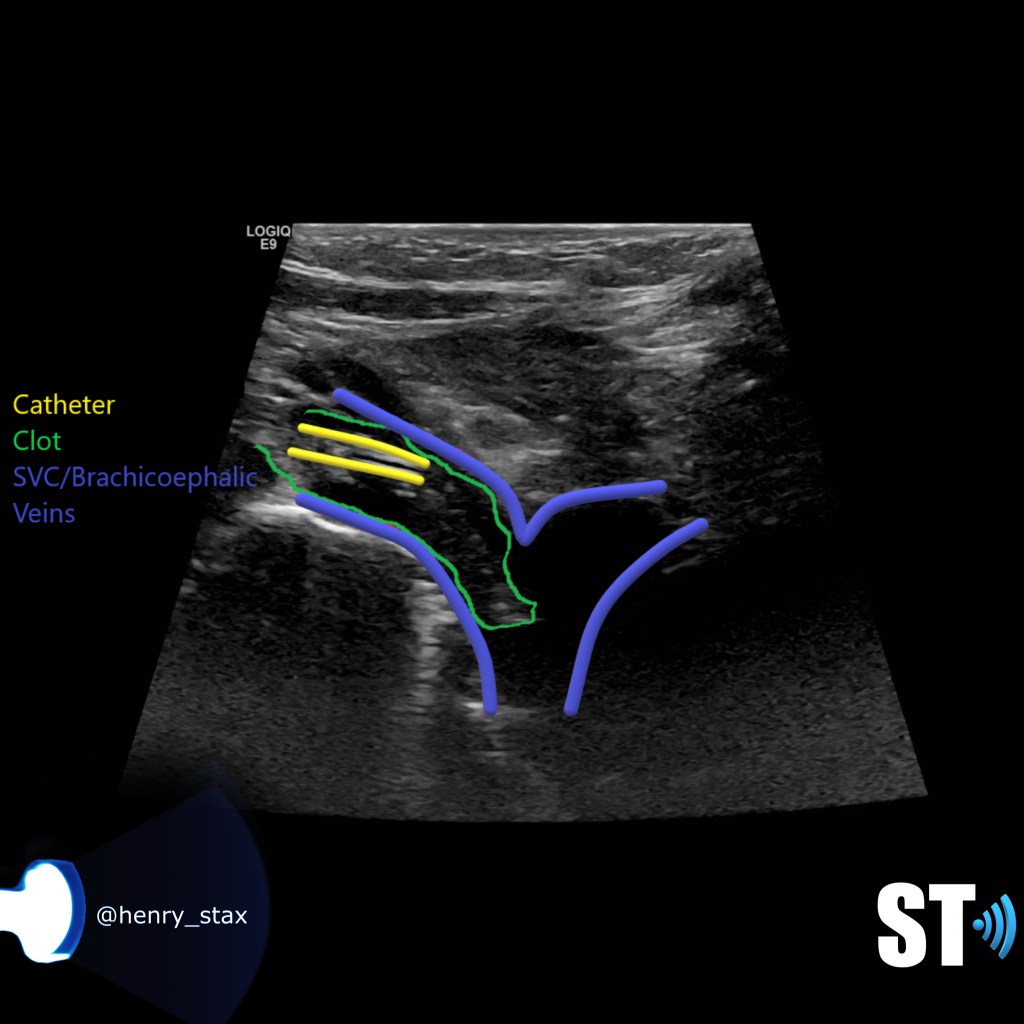

Thrombosis of the right innominate vessel with indwelling catheter